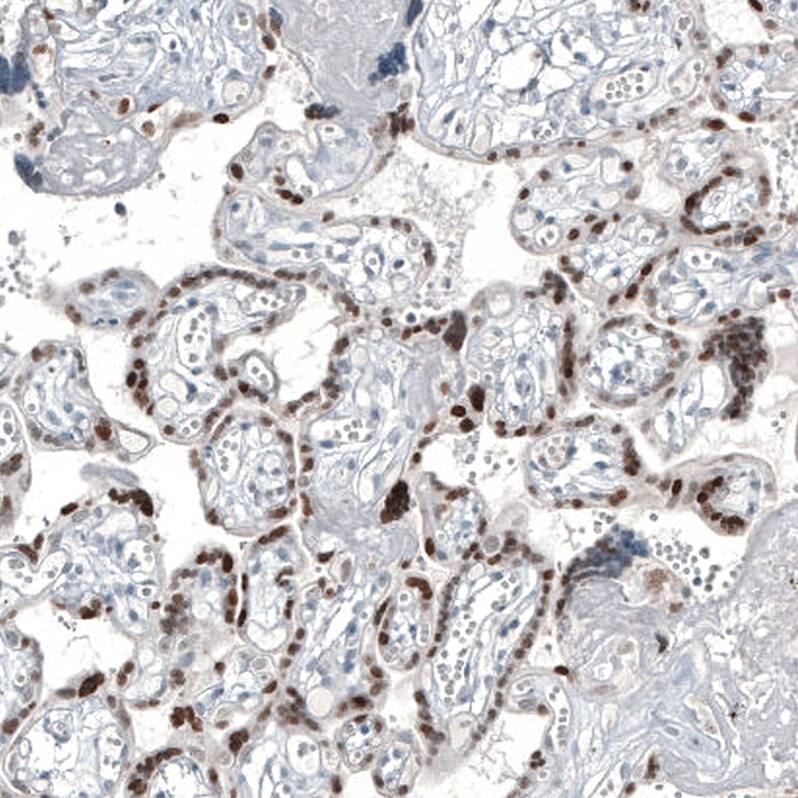

Immunohistochemistry-Paraffin: GATA-3 Antibody [NBP3-44195]

Staining of human breast cancer shows moderate to strong nuclear positivity in tumor cells.Immunohistochemistry-Paraffin: GATA-3 Antibody [NBP3-44195]